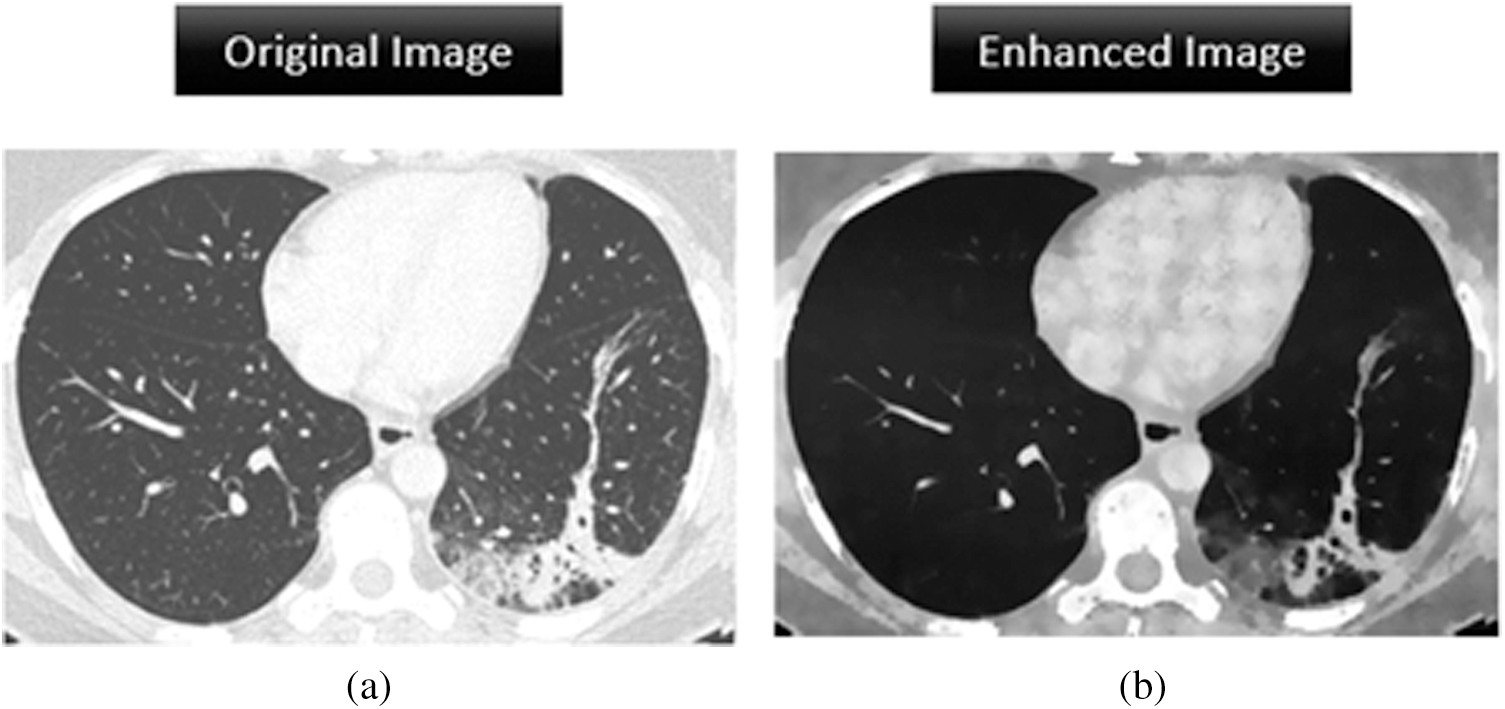

The BRISQUE is used for automatic image analysis in the spatial domain. We implemented image quality assessment in MathWorks MATLAB 2019a. The BRISQUE has been applied to magnetic resonance images [29] demonstrating evaluation reliability for medical images. Fig. 10 shows the image quality results of a chest CT scan before and after enhancement. The BRISQUE score falls from 135.25 to 46.25 after enhancement, representing a 65% decrease that demonstrates the effectiveness of the proposed image enhancement pipeline, which provides suitable images for COVID-19 detection.

Figure 10: Image enhancement analysis of the original image and the processed image by assigning a BRISQUE score. (a) BRISQUE score = 135.25 (b) BRISQUE score = 46.25